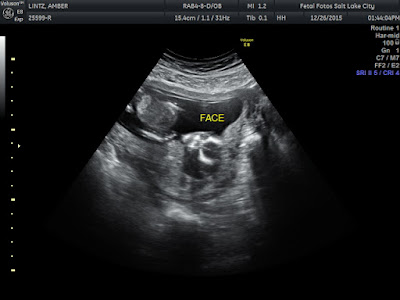

We got right back into our appointment and told the tech to not tell us if she figured it out to have us close our eyes. We asked her to tell Gage after the appointment, same thing we did with Nash. Right away she had us close our eyes and said she was pretty sure already but wanted to be 100%. The cord was between the legs and she wanted to get it out of the way. She did some pokes and had me lay on my side for a few minutes. When she came back in she had us close our eyes and said "oh there we go, don't open your eyes!" she was super confident and that made me think right away boy! The rest of the ultrasound went perfectly. Baby had its head into my back so we got a lot of alien looking pictures. I love seeing the heart beating away. Baby was moving its hands all over the place, and moving a ton! We finished up and left Gage in the room. At this point I was pretty sure my boy thoughts were correct until Gage came out of the room. You could tell he was trying to have a poker face but he looked pissed. Tyler and I both laughed and told him to look away so he didnt give it up! She put the results in a green envelope and we went into the car. We pulled out our camera and recorded him telling us that it was a BABY SISTER!

It was such a special day! Today 2 days later I watched the video they give you of the ultrasound. It was fun to be able to see the parts she made us close our eyes for. This baby is for sure a girl. With both my boys you could instantly tell they were boys. With this baby there was nothing between the legs and those 3 lines they search for.